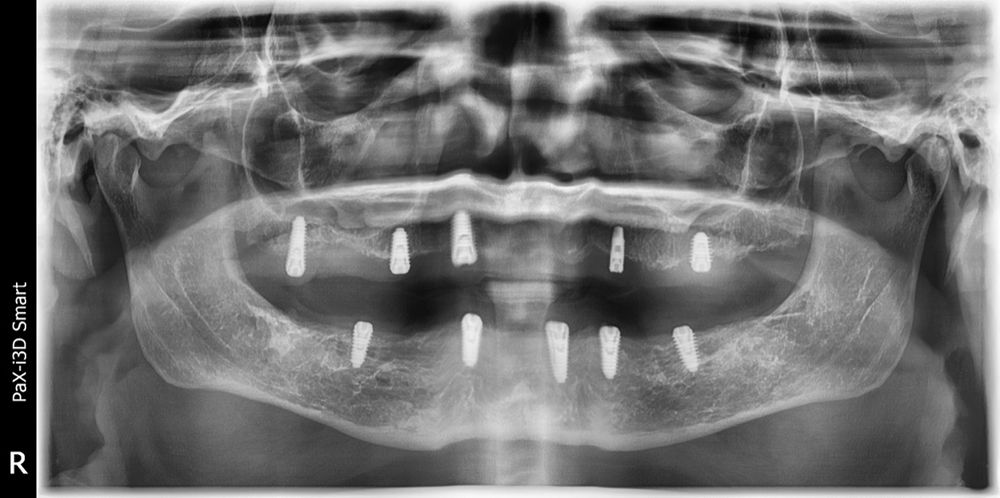

Looking back at this x-ray, Dr Gupta was not happy that almost every implant in the maxilla has threads showing above the bony crest (Figure 2).